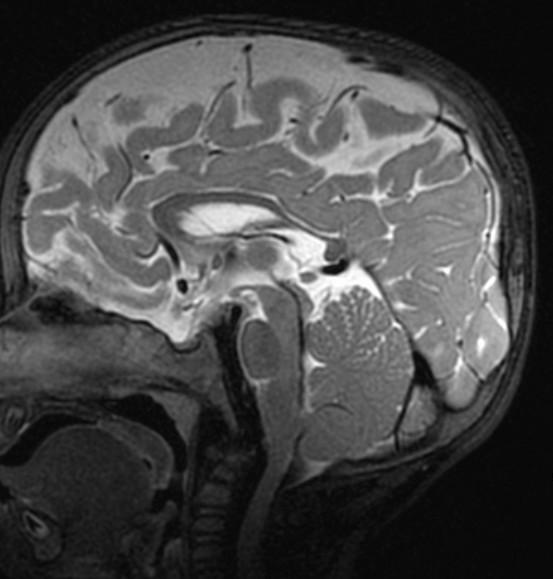

Sag T2 Cube nongated Normal

Normal

Sag T2 Cube

Nongated: CSF dephasing in the aqueduct on this sequence

Primary fissure 3 lobes Closed fastigial point

Sag T2 Cube Normal